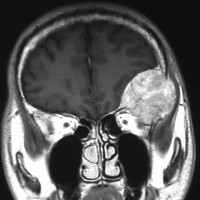

40代女性の後頭部傍矢状洞部の硬膜に発生したグレード3です。腫瘍周囲の強い浮腫のために,頭頂葉のゲルストマン症候で発症しました。術前診断は髄膜腫でしたが,腫瘍内部にのう胞(液体が溜まっている)があり,髄膜腫としては典型的な画像ではありません。右側の血管撮影にみられるように,上矢状洞が一部狭窄して腫瘍が浸潤している所見があり,腫瘍が濃染します。腫瘍の周囲の脳には出血がありました。大脳鎌と上矢状洞の壁を含めて全摘出しました。